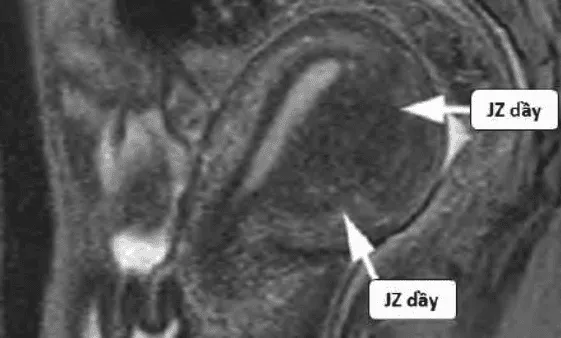

Thuyết tử cung hai nguồn gốc: Tử cung phát triển từ hai nguồn Muller và trung mô, gặp nhau tại vùng kết nối (JZ). Adenomyosis xuất phát từ chồng lấn bất thường tại JZ.

Hình ảnh “Adenomyosis trên MRI”.

MRI: Phân biệt adenomyosis vs u xơ, đánh giá lạc nội mạc sâu.